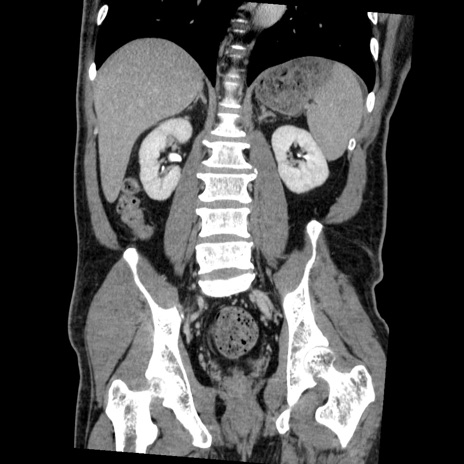

症例22(冠状断像)

【症例】50歳代男性

【主訴】腹痛

【現病歴】AVMからの被殻出血のため回復期リハ病棟入院中。 本日午後3時頃急に下腹部痛が出現した。

【既往歴】AVM、被殻出血、虫垂炎、高血圧

【身体所見】意識晴明、左半身不全麻痺、会話の理解は良好、36.5°C、腹部:膨隆、全体に板状硬、下腹部正中に圧痛点あり、反跳痛-、筋性防御不明、右下腹部にope scar

【データ】WBC 9400、CRP 0.06